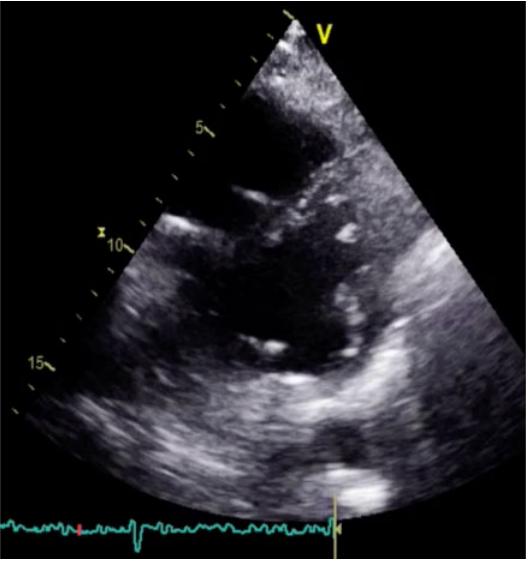

超声心动图显示右心室重新扩张,有轻度功能障碍,并有容量超负荷的迹象(图1),存在严重三尖瓣反流和严重肺动脉高压,左心室并无改变。

图1,术前超声心动图显示容量超负荷迹象